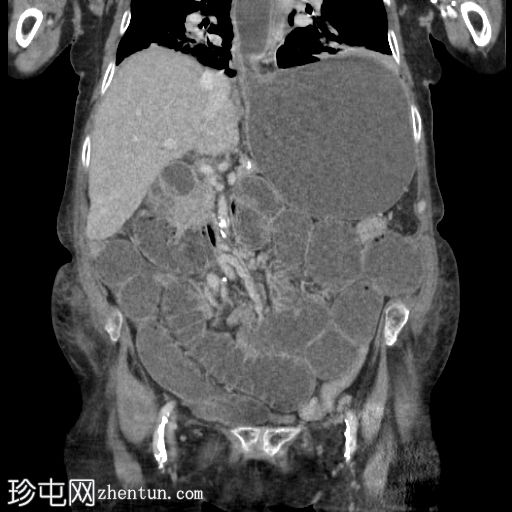

冠状位增强扫描(门静脉期)

可见一大型上腹疝,内含部分结肠,矢状位图像亦可见。

另可见一小型右侧闭孔疝,内含脂肪。冠状位图像亦可见。

未发现胸腹部恶性肿瘤。